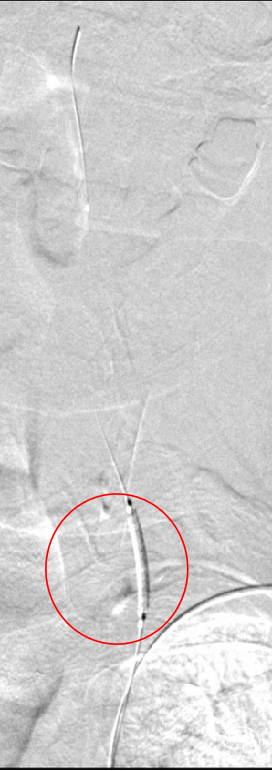

支架定位及释放:

沿导丝将4.0mm*16mm Bridge椎动脉雷帕霉素靶向洗脱支架送到目标位置,确认定位准确后,以骨性标志为参考,缓慢加压释放支架,造影确认支架位置准确。

术前术后对比:

术前

术后

随访:患者术后一般情况好,神经系统查体无明显异常,复查头颅CT未见新发梗死/出血,血压控制良好,好转出。